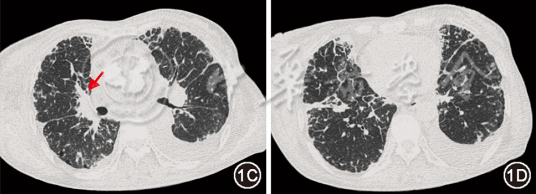

图1  治疗前(2024年9月10日)胸部CT:双肺弥漫网格(图1B红箭头)、磨玻璃影(图1B黄箭头),小叶间隔增厚(图1A箭头),支气管血管束增粗(图1C箭头)

本例患者影像表现为支气管血管束增粗、小叶间隔增厚、磨玻璃及网格影,呈“淋巴道分布模式”,伴纵隔淋巴结肿大、胸膜增厚及胸腔积液。在接诊“淋巴道分布模式”的肺间质病变患者时,应鉴别癌性淋巴管炎、结核感染、结节病等疾病。患者虽为老年女性,有右乳肿大,但病情发展相对缓慢,影像提示淋巴水肿,故除外癌性淋巴管炎。患者T-SPOT.TB阳性,纵隔淋巴结病理见炭末沉积,伴多核巨细胞,在难以明确诊断时,接受诊断性抗结核治疗,然而效差,除外结核感染。患者影像也符合结节病表现,且血ACE升高,对结节病有一定提示意义,但结节病中ACE阳性率不足50%,其他疾病如肺结核也可升高,故其阳性不能作为结节病诊断标准[1, 2];此外,患者伴顽固性胸腔积液,在结节病中少见[3];BALF淋巴细胞占比低,激素治疗无效,排除结节病诊断。此外,尘肺病及肺淋巴管疾病亦有类似表现,应予鉴别。